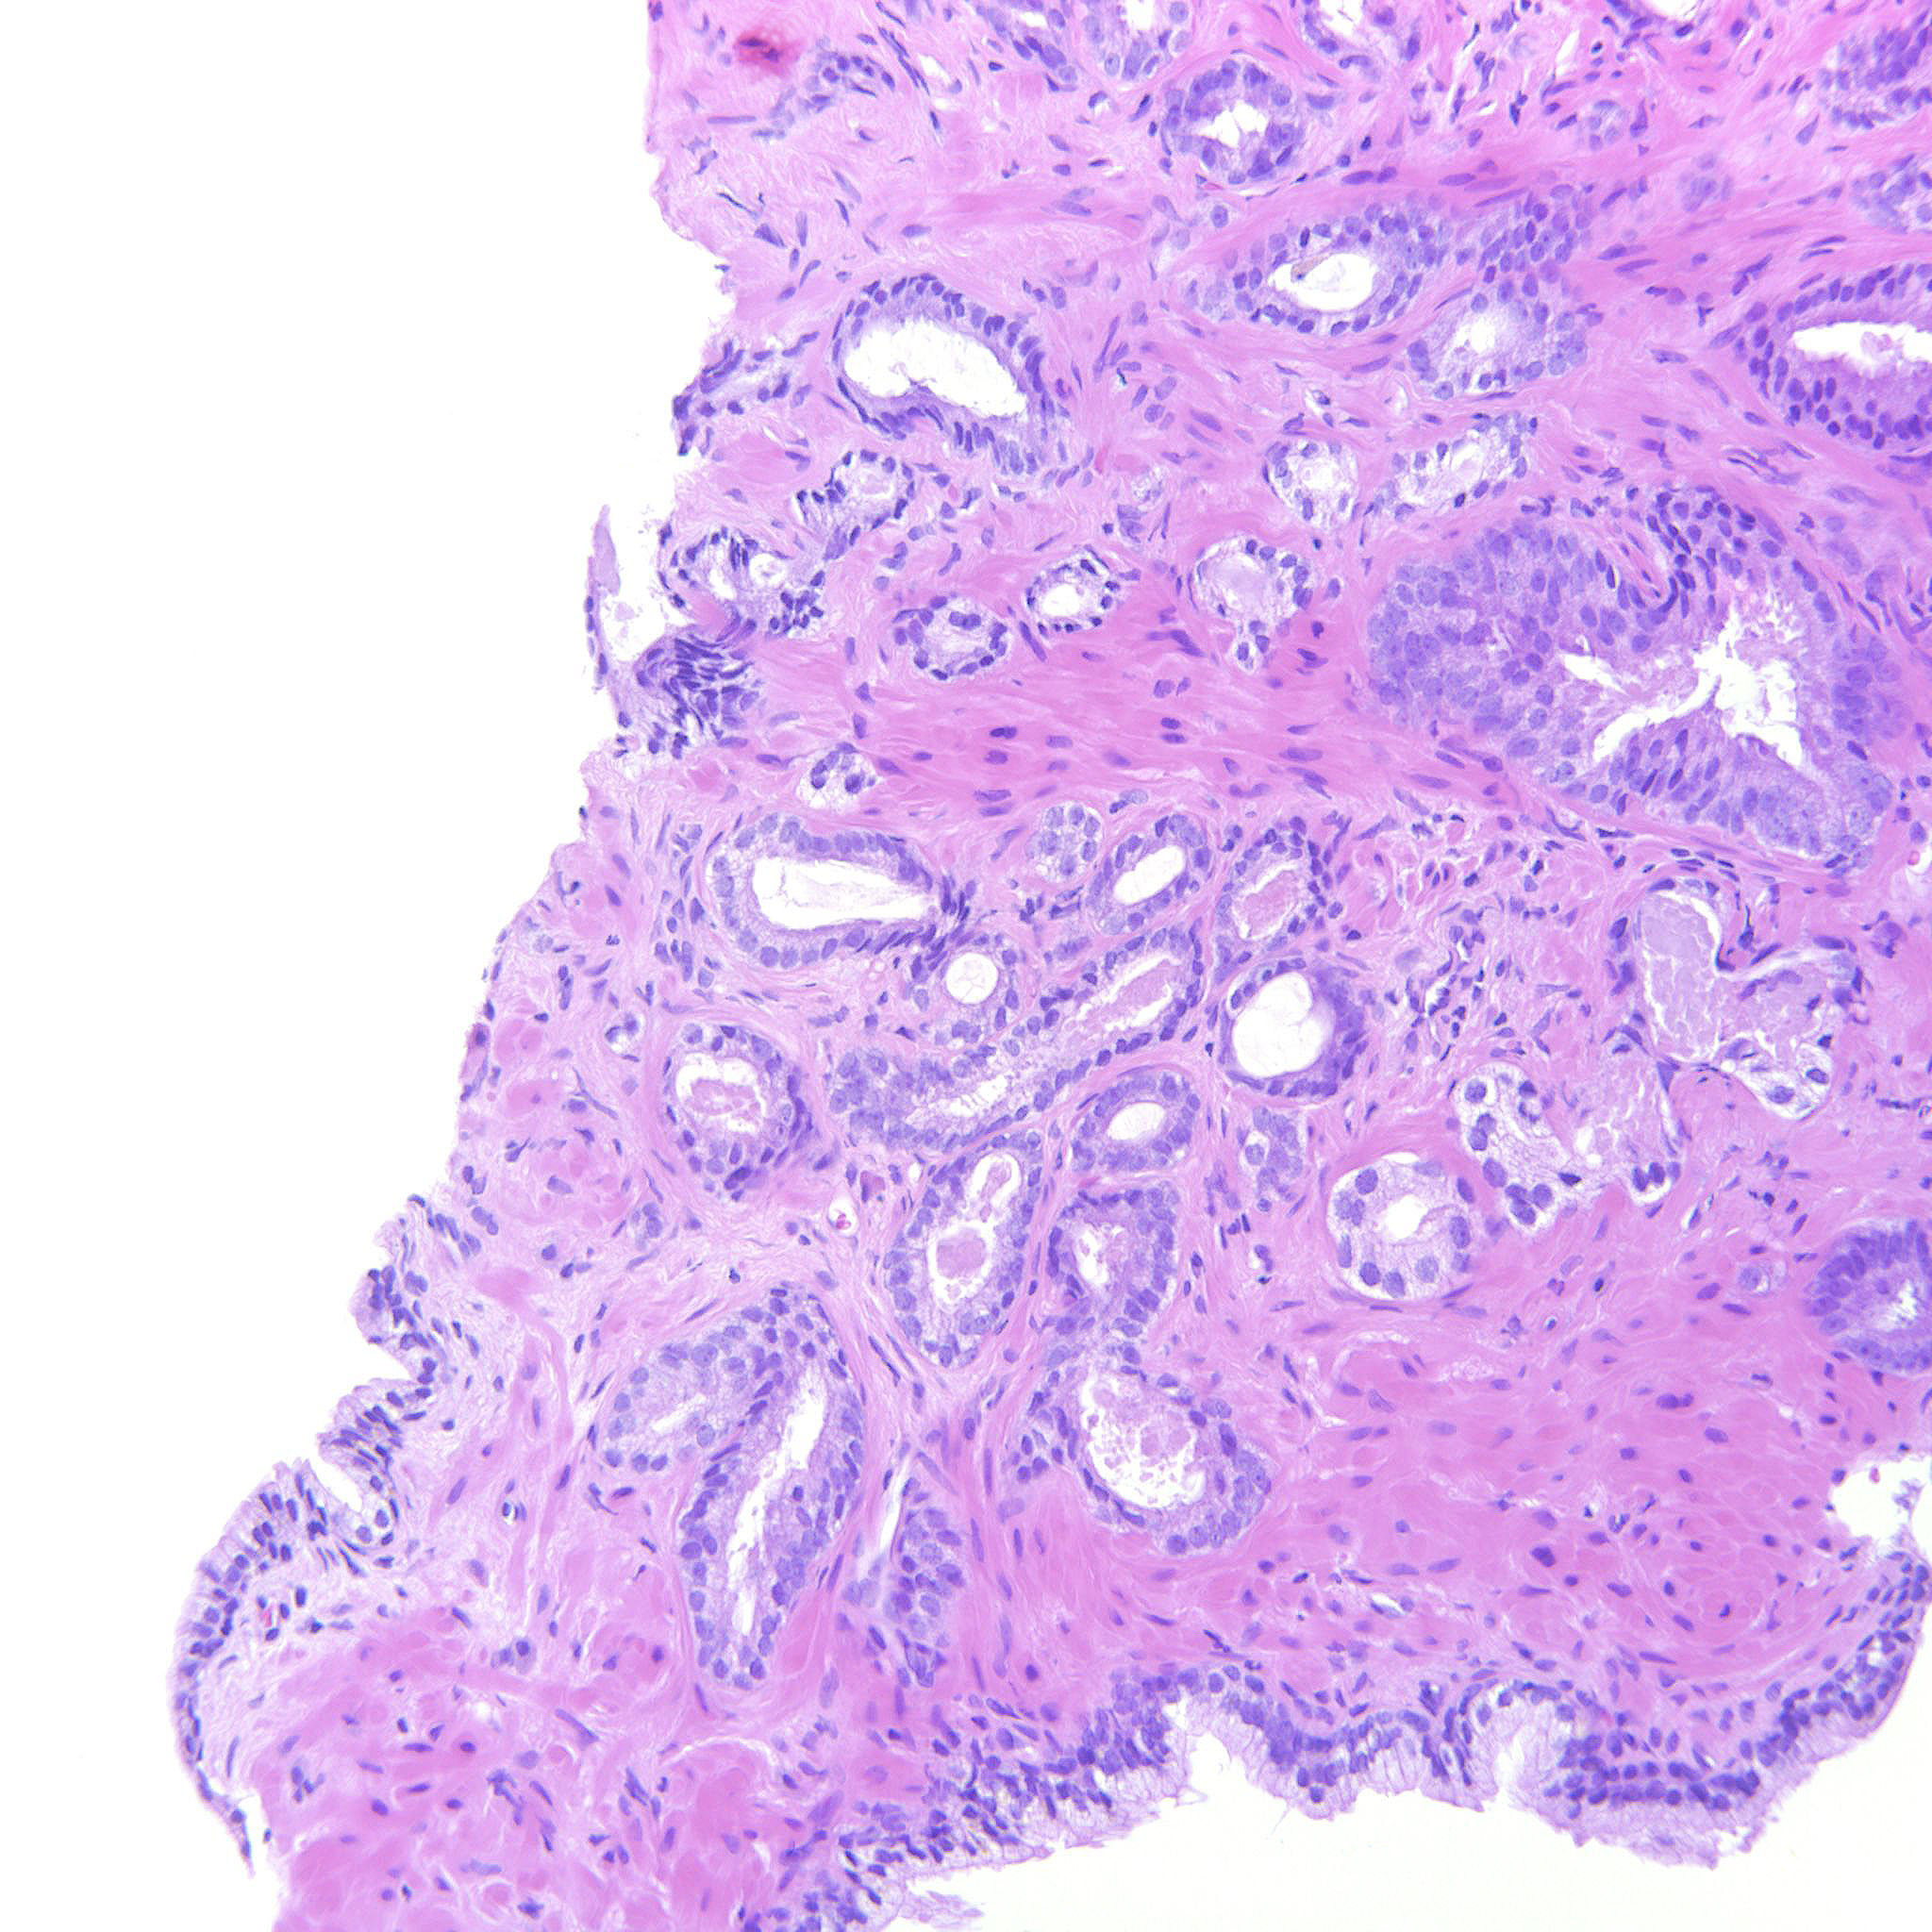

Prostate cancer grading

Case ID: 314